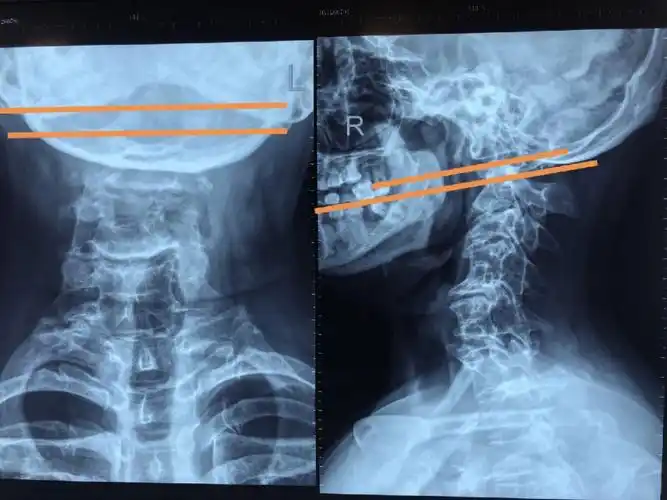

颅底凹陷症